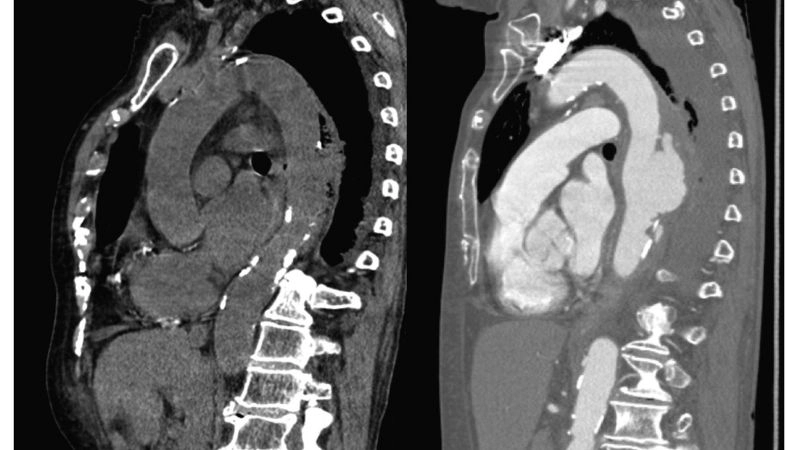

Aortitis diagnosis with advanced medical imaging

Aortic aneurysm as a complication of aortitis